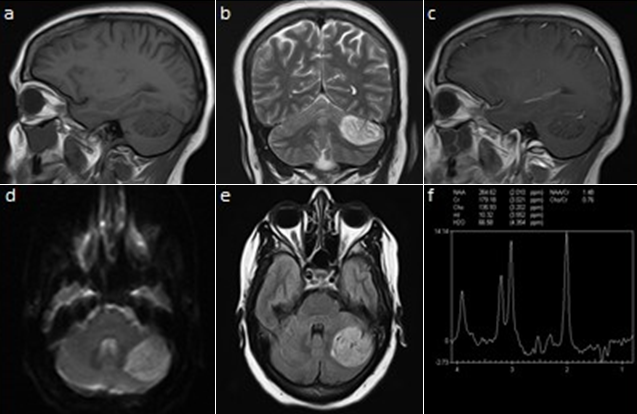

A 42-year-old female presented with complaints of mild occipital headaches of severe months duration. There were no cutaneous lesions or significant family history suggesting any genetic disease. On examination, she did not have any papilloedema, dymetria, dysdiadokokinasia or ataxia. Her cranial nerve examination was normal. On non-enhanced computed tomogram (CT) showed a mildly hyperdense well circumscribed lesion, in the left upper cerebellar hemisphere with no bone involvement (not schown). MRI showed an intra-axial lesion measuring 3.7cm × 3.5cm × 2.5cm in relation to the tentorium cerebelli and lateral sinus which was hypointense on T1-weighted image (T1WI) (A), with the characteristic striated appearance or "tiger-striped" appearance on T2-weighted image (T2WI) (B), there was no apparent contrast enhancement (C). This lesion was hyperintense in diffusion (D) and in fluid attenuation inversion recovery (FLAIR) (E). There was no extension into the internal auditory canal. There was no compression of the brainstem and ventricular system. Proton (¹H) MR spectroscopy study (MRS) revealed normal N-acetyl-aspartate (NAA)/Creatine (Cr) ratio (1.48), moderately decreased choline (cho)/Cr (0.76) (F). An abdominal ultrasound was performed in order to evaluate the intraabdominal organs and found to be normal. She has been under routine follow-up for 3 years. On the last control, the brain MRI showed lesion stability. Given the well-tolerated nature of her headaches and the stability of the lesion, the staff of the neurosurgeons indicated a routine control without surgery.